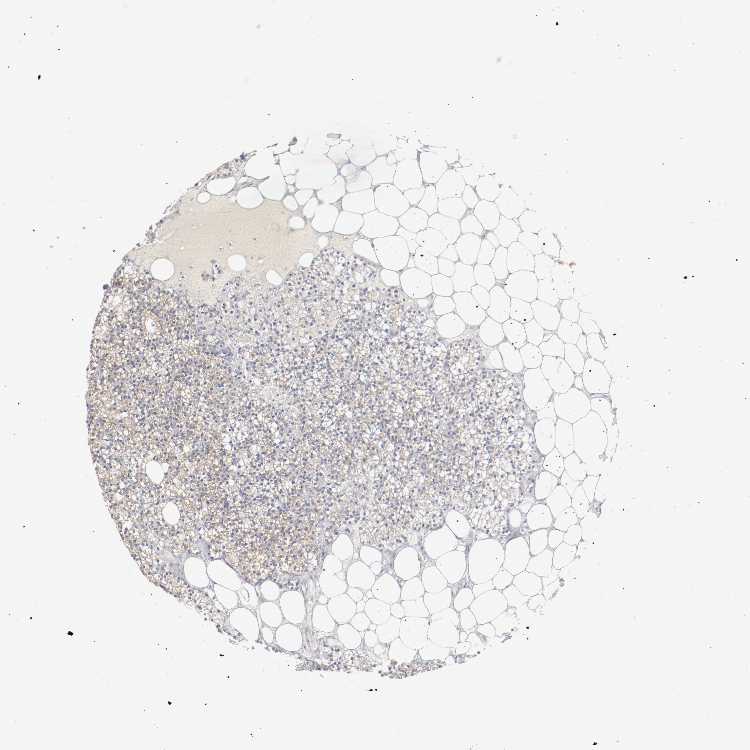

TISSUE PRIMARY DATA PARATHYROID GLAND Show tissue menu

PARATHYROID GLAND - Antibody stainingi

Antibody staining in the annotated cell types in the current human tissue is reported as not detected, low, medium, or high, based on conventional immunohistochemistry profiling in selected tissues. This score is based on the combination of the staining intensity and fraction of stained cells.

Each image is clickable and will lead to virtual microscopy that enables deeper exploration of all samples and also displays staining intensity scores, fraction scores and subcellular localization as well as patient and tissue information for each sample.

Antibody HPA000864Antibody CAB012232Antibody CAB012520

Glandular cells MediumHighHigh